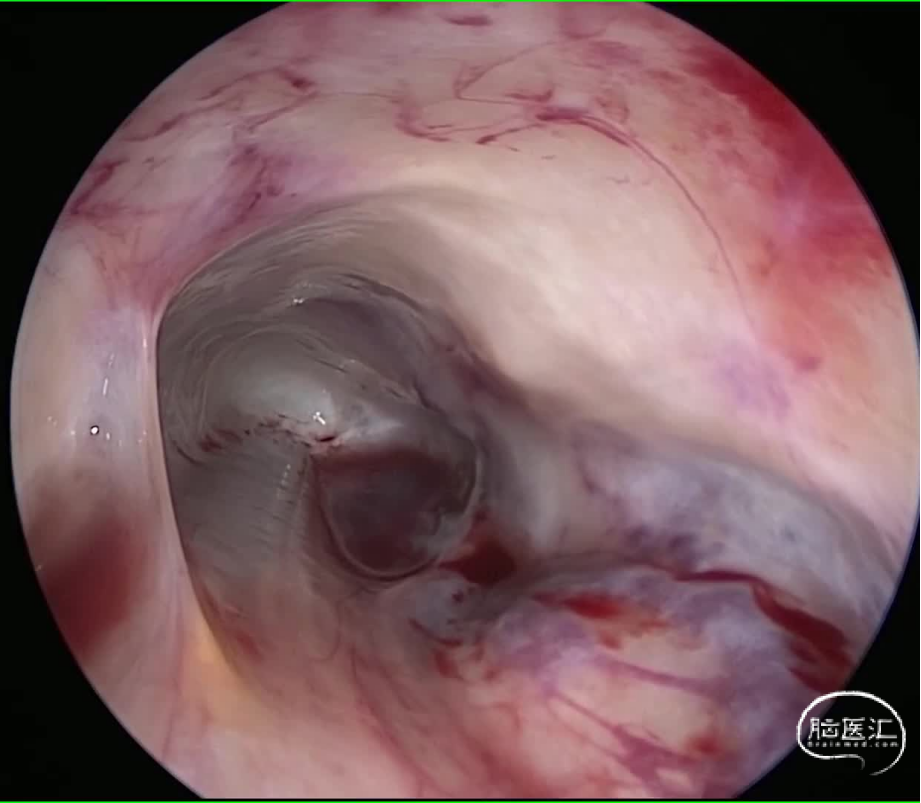

中山大学肿瘤防治中心影像医学中心的刘海彬医师为患者手术提供了高质量的影像学资料,为制定手术方案提供了很大的帮助。完善相关检查,经由神经外科脊髓脊柱亚专业组MDT讨论,萧女士的T11-L3椎管内硬膜间占位行囊腔探查术+漏口修补术。电生理监测,根据术前影像学可大致定位漏口位于L1水平,单个椎板暴露,术中用角度内镜探查确认漏口位置,避免过度牵拉脊髓及神经根,避免加重神经功能障碍,维护脊柱稳定性,是该手术的目标。张继教授阅片后指出:T11-L3椎管内病灶,考虑硬脊膜囊肿可能性大,单个椎板暴露,双镜联合下探查漏口位置,实现预定手术目标(自体组织修补漏口,缓解术前症状),为神经功能恢复创造条件。避免已经变薄硬脊膜和蛛网膜破损,减少了蛛网膜下腔血性脑脊液刺激的概率。

图2 手术过程: 病灶位于硬脊膜夹层见,见清亮脑脊液,有多个分隔,内镜下探查并开通数个分隔,漏口位于L1水平,以自体组织进行修补交通口。